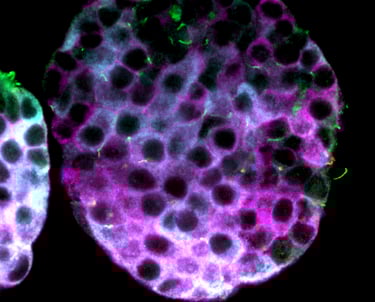

Immune infiltration in T1D

T cells (green) replacing entire islet